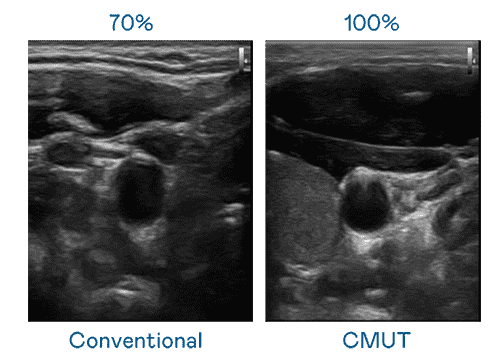

CMUT 技术是一种用电容式微机电元件来产生超音波讯号的技术。。。。与传统 PZT 压电式技术相比,,,CMUT 频宽增加 30%,,,更宽频的超音波讯号让影像解析度大幅提升,,,是实现高影像品质医疗超音波扫描、、、促进精准医疗发展的关键技术。。

大频宽带来超清晰影像

超音波影像的解析度高低,,首先取决于探头能发出的讯号频宽。。。杏悦2 CMUT 可提供高清晰的超音波讯号,,提供高频宽、、高灵敏度、、影像纹理细节更高的超音波影像,,协助医护人员缩短影像判读时间及利用精准的医疗影像进行诊断。。